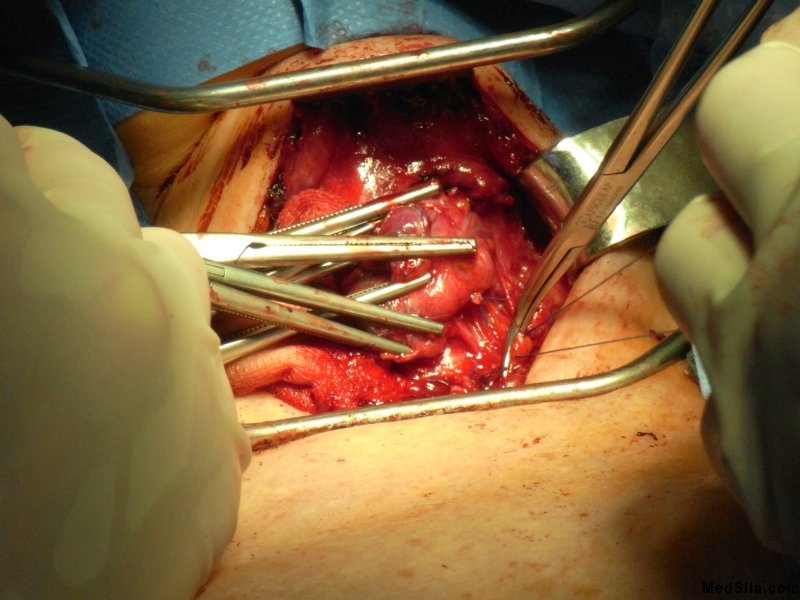

Этапы операции.

Хирурги вначале удаляют ту часть щитовидной железы, в которой расположен узел. Этот материал подвергается экспресс анализу. И если анализ подтверждает наличие опухолевых клеток в узле, хирург расширяет оперативное вмешательство до экстрафасциальной тиреоидэтомии с двухсторонней лимфодиссекцией.

В случае, когда экспресс метод отрицает наличие злокачественных клеток, операция заканчивается на удаление только одной части железы. Удаленная часть железы повторно проверяется другой лабораторией и уже через несколько дней (около 3-4) приходит окончательный результат. К сожалению, может случиться так, что экспресс метод не подтвердит рак, а вот окончательное исследование все-таки выявит атипичные клетки. Тогда хирургам придется произвести повторное оперативное вмешательство и удалить оставшуюся часть железы вместе с лимфатическими узлами.